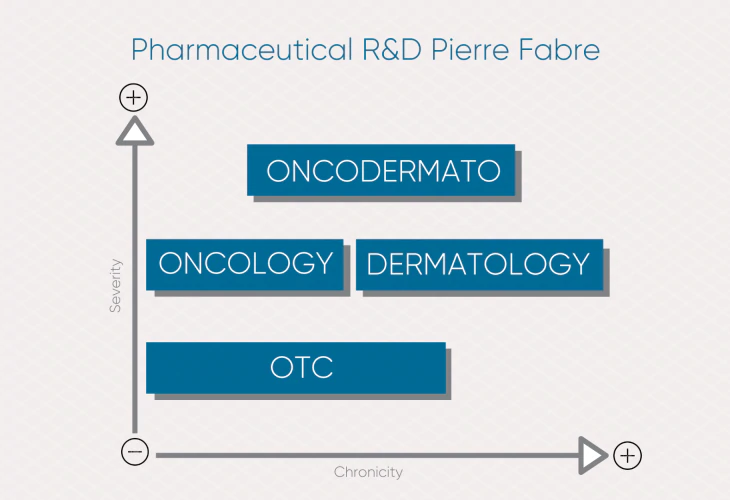

Domaines de recherche pharmaceutique

Pierre Fabre investit dans 4 axes de recherche pharmaceutique pour concevoir des solutions innovantes et apporter des réponses thérapeutiques à des besoins non satisfaits.

Notre recherche intégrée et transversale, de la santé à la beauté, génère de la valeur pour les patients et les professionnels de la santé.